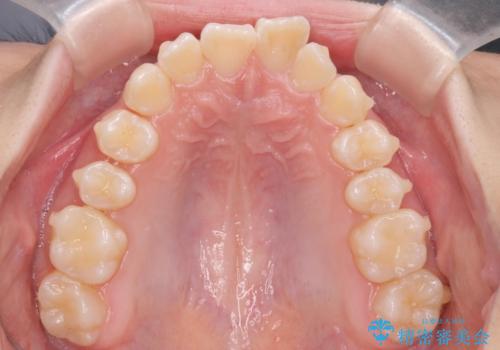

子供の出っ歯 生え代わりと成長期を利用して非抜歯で矯正

- 出っ歯を主訴に来院。

生え代わりを待ってから矯正を始めました。

特に右側のかみ合わせがずれていたため、上の奥歯を後ろに下げています。

下顎も前方に成長し、前歯のかみ合わせも同時に深かったのを浅くすることができました。